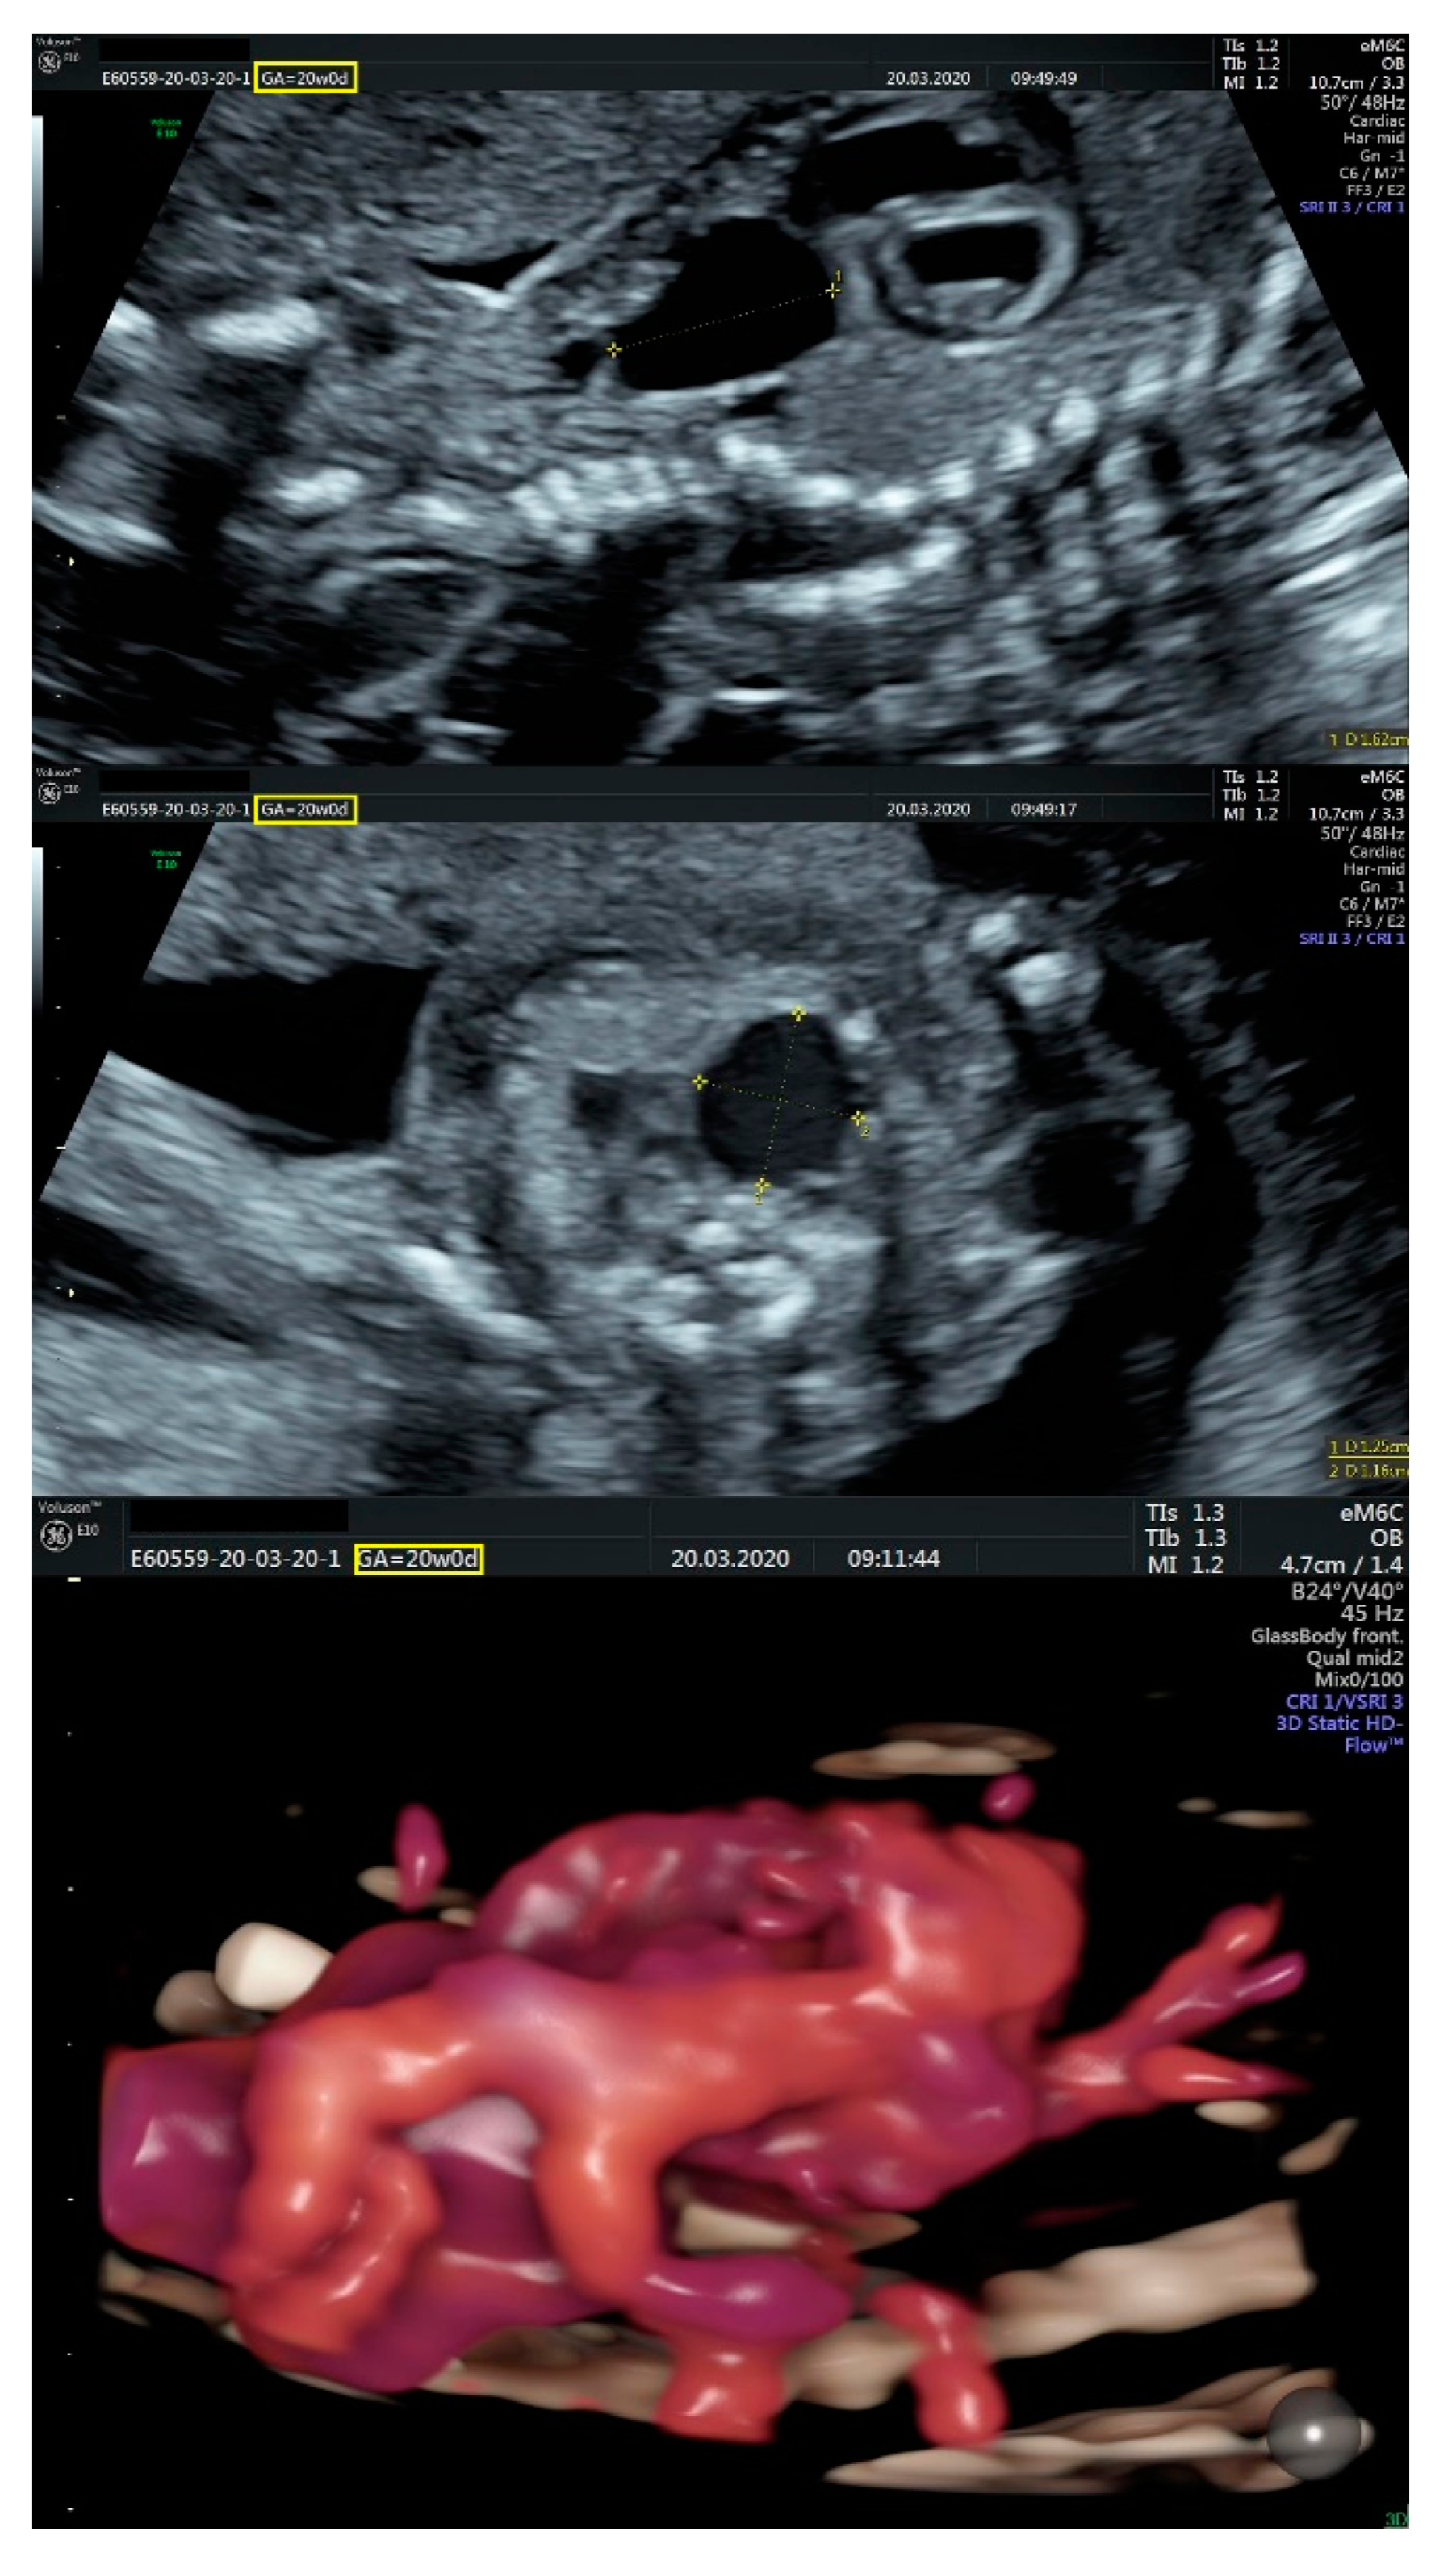

- an isolated aortic arch anomaly (supposedly aneurysmal dilation from which the left common carotid artery emerges) and coarctation of the aorta with the anterograde flow;

- ventricular septal defect, coarctation of the aorta, and a vascular formation located superior from the aortic arch with the appearance of an arteriovenous fistula;

- aneurysmal dilation located above the pulmonary trunk bifurcation and a dilated left common carotid artery with a retrograde flow;

- minor ventricular septal defect with a normal ductus venosus triphasic flow.